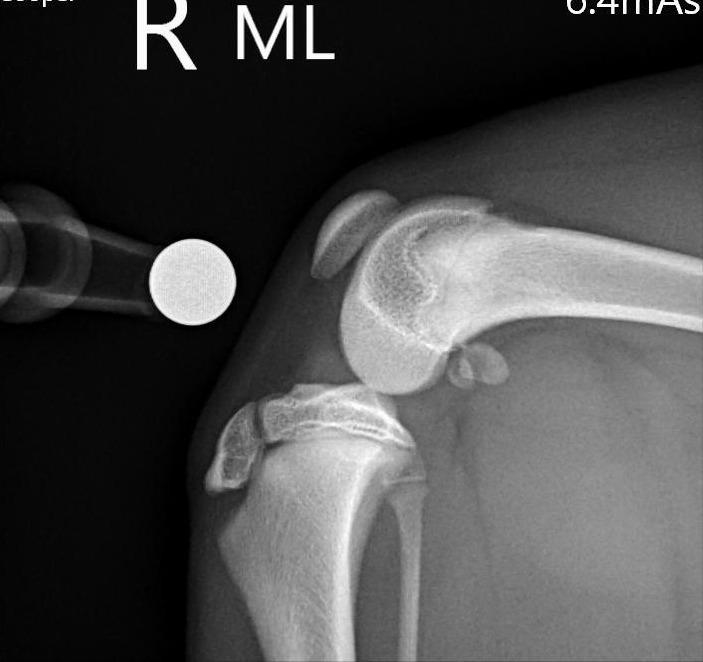

我們練習一下: 第一張照片R是正常的膝蓋, 找找看標記L的第二張 部分哪裡飛起來了呢?